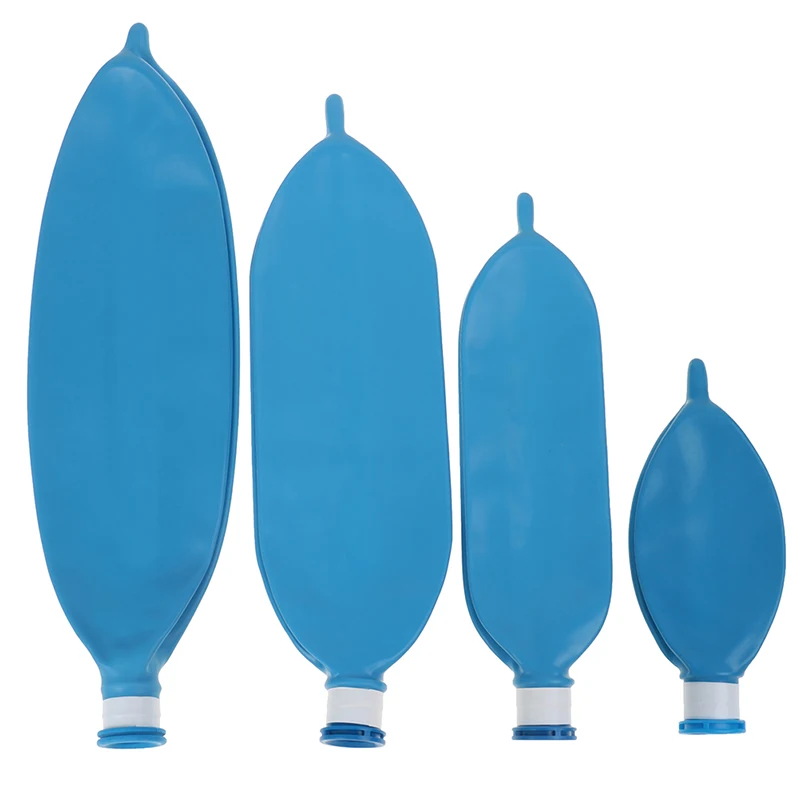

Латексный одноразовый дыхательный аппарат для анестезии объемом л, 1 л, 2 л, 3 л

Описание:Материал: латексРазмер: 0.5л 1Л 2л 3лЦвет: синий